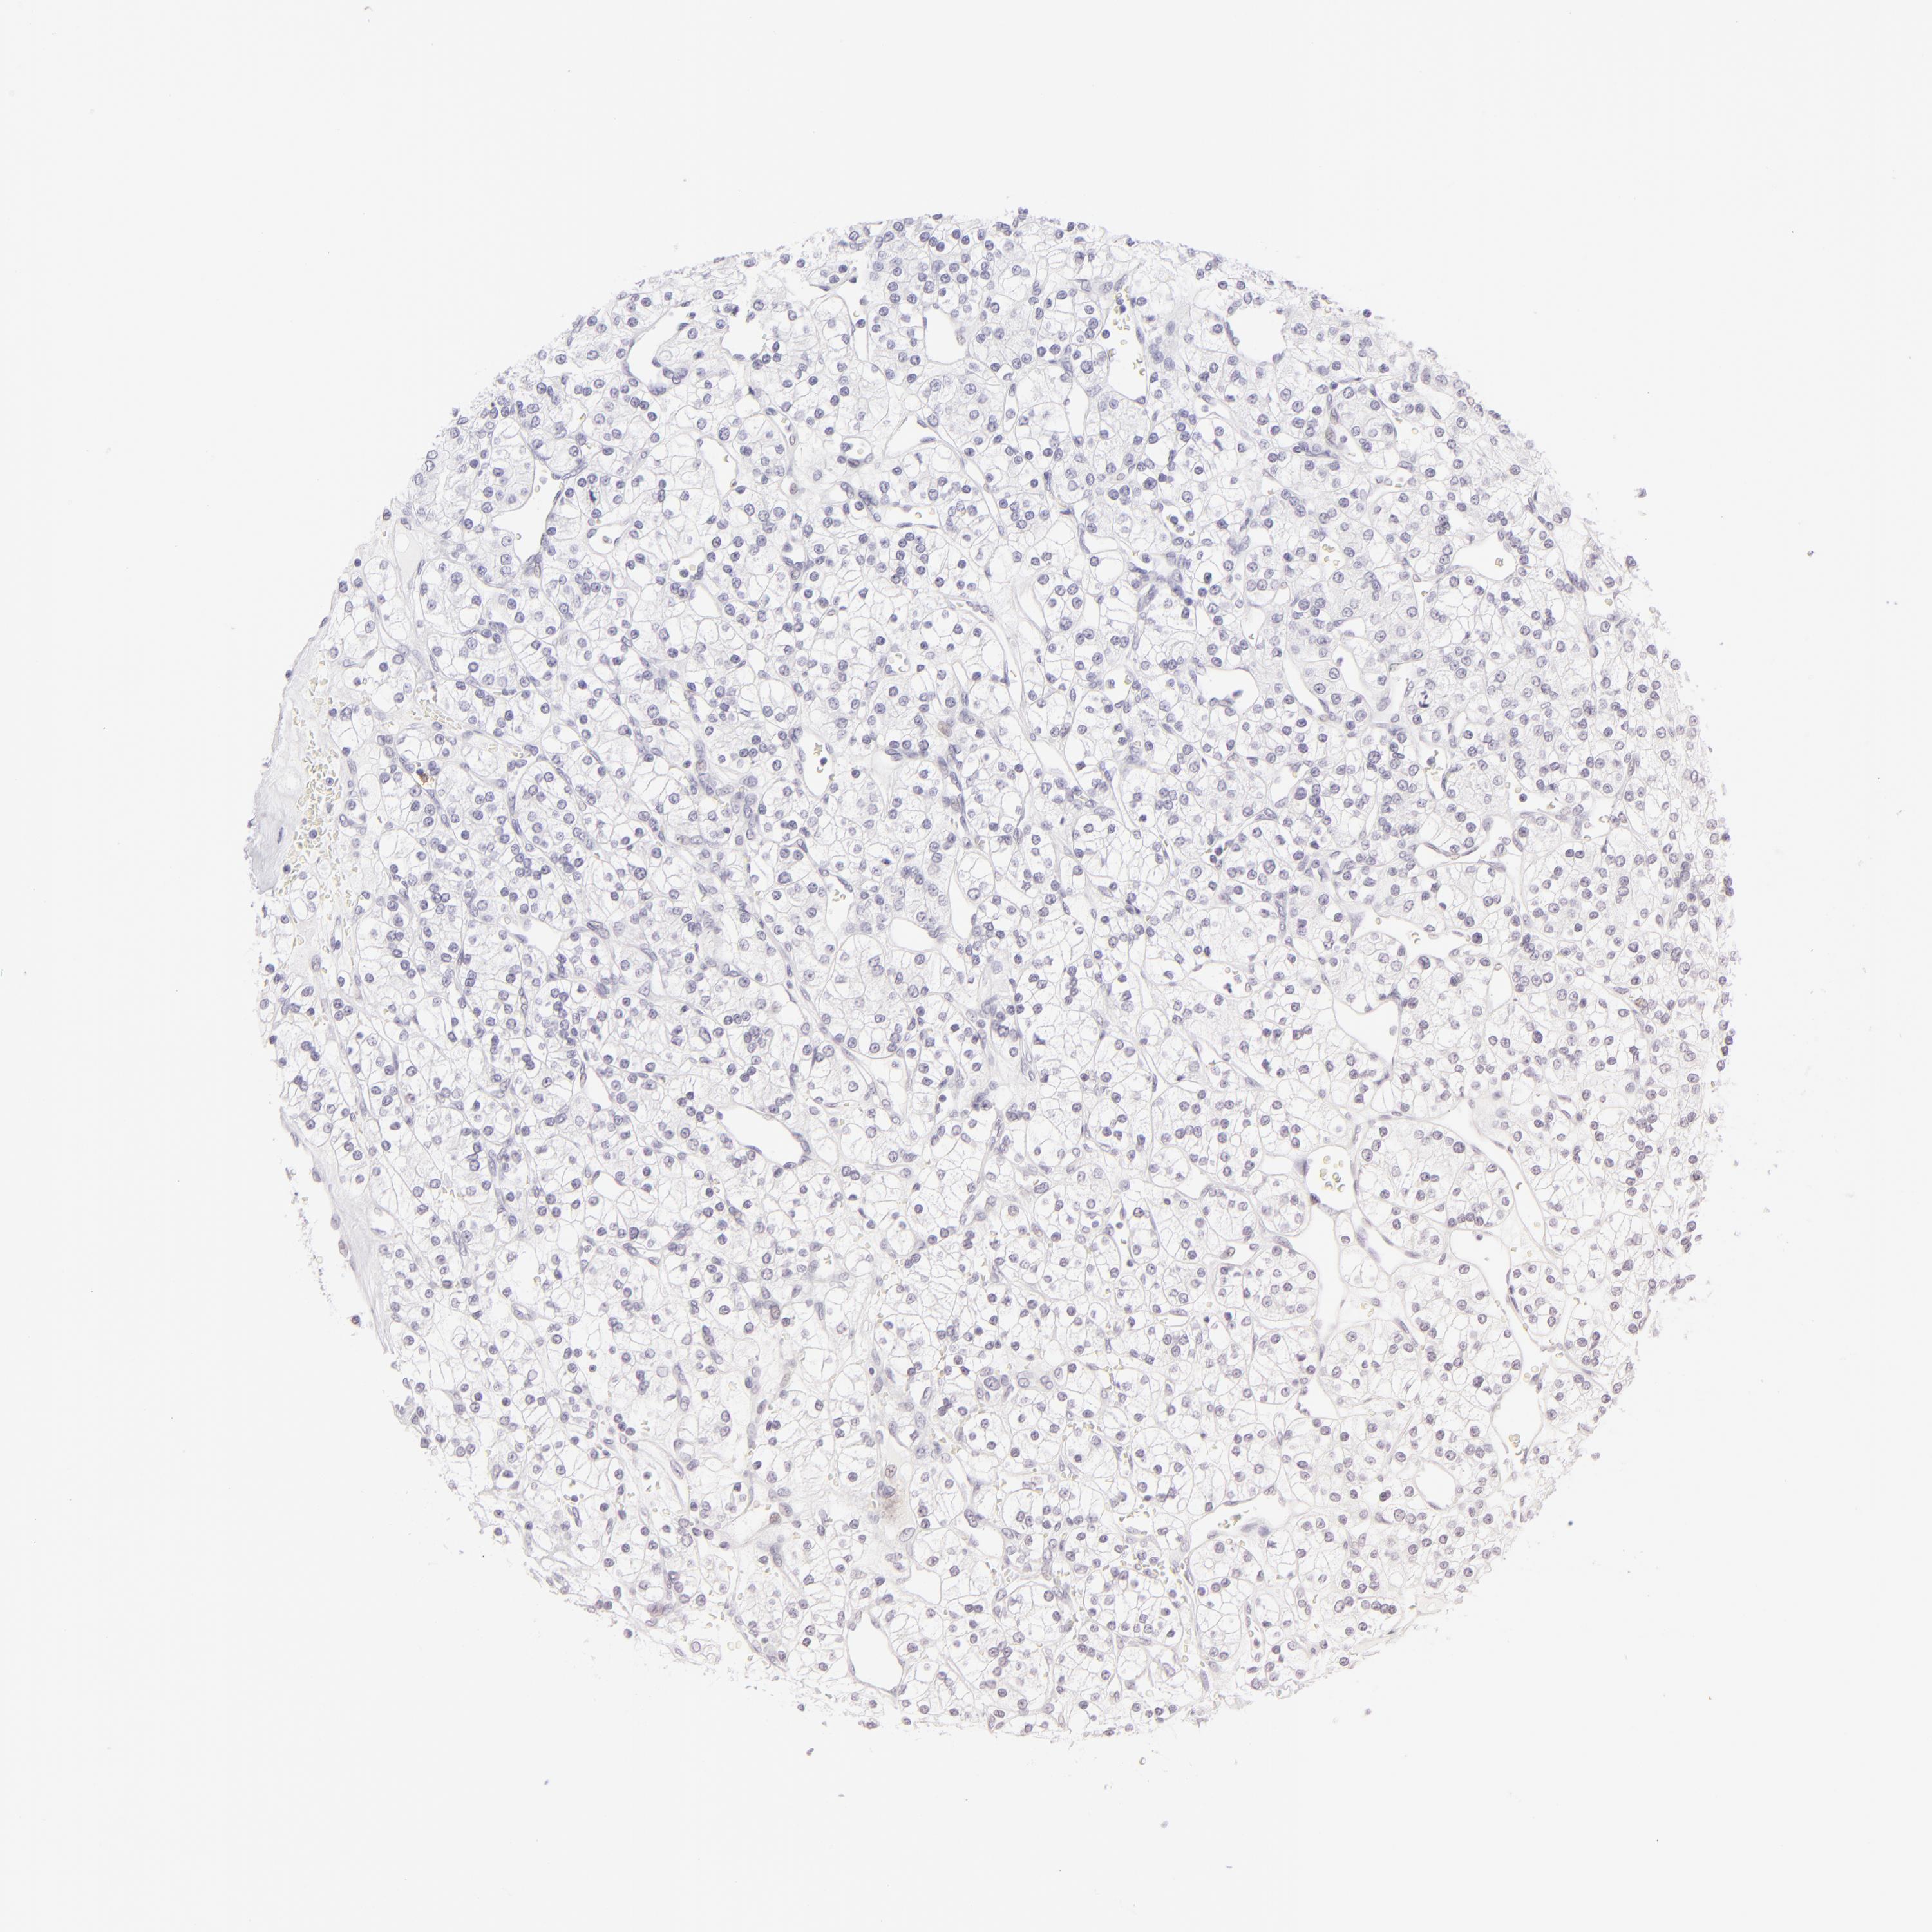

KIDNEY RENAL CLEAR CELL CARCINOMA (VALIDATION) - Interactive survival scatter ploti

The Survival Scatter plot shows the clinical status (i.e. dead or alive) for all individuals in the patient cohort, based on the same data that underlies the corresponding Kaplan-Meier plots. Patients that are alive at last time for follow-up are shown in blue and patients who have died during the study are shown in red.

The x-axis shows the expression levels (FPKM) of the investigated gene in the tumor tissue at the time of diagnosis. The y-axis shows the follow-up time after diagnosis (years). Both axes are complimented with kernel density curves demonstrating the data density over the axes. The top density plot shows the expression levels (FPKM) distribution among dead (red) and alive patients (blue). The right density plot shows the data density of the survived years of dead patients with high and low expression levels respectively, stratified using the cutoff indicated by the vertical dashed line through the Survival Scatter plot. This cutoff is automatically defined based on the FPKM cutoff that minimizes the p-score. The cutoff can be changed by dragging the vertical line or by entering a cutoff value in the square labeled "Current cut-off".

Under the Survival Scatter plot the p-score landscape (black curve; left axis) is shown together with dead median separation (red curve; right axis). Dead median separation is the difference in median mRNA expression between patients who have died with high and low expression, respectively. It is calculated as follows: median FPKM expression of dead patients with high expression - median FPKM expression of dead patients with low expression. This is intended to aid the user in visually exploring custom cutoffs and the associated p-scores and dead median separation.

Individual patient data is displayed and can be filtered by clicking on one or more of the category buttons on the top of the page. Categories describing expression level and patient information include: high, low, alive, dead, female, male and tumor stages. The scale of the x-axis can be toggled between linear and log-scale by clicking on the "x log" button. Mouse-over function shows TCGA ID, patient information and mRNA expression (FPKM) for each patient.

& Survival analysisi

Kaplan-Meier plots summarize results from analysis of correlation between mRNA expression level and patient survival. Patients were divided based on level of expression into one of the two groups "low" (under cut off) or "high" (over cut off). X-axis shows time for survival (years) and y-axis shows the probability of survival, where 1.0 corresponds to 100 percent.

FCER2 is not prognostic in Kidney Renal Clear Cell Carcinoma (validation)

TCGA RNA samplesi

RNA-seq data is reported as average FPKM (number Fragments Per Kilobase of exon per Million reads), generated by the The Cancer Genome Atlas (TCGA) .

Normal distribution across the dataset is visualized with box plots, shown as median and 25th and 75th percentiles. Points are displayed as outliers if they are above or below 1.5 times the interquartile range. FPKM values of the individual samples are presented next to the box plot.

Average pTPM 0.2

Number of samples 100